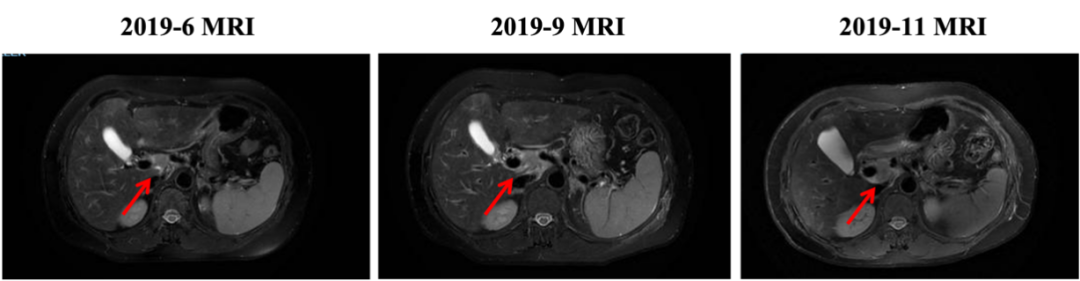

▌四线治疗:

2019-11开始换用吡咯替尼联合长春瑞滨治疗,最佳评效:SD。2020-11新发肝转移病灶,评效PD,PFS为12月。不良反应:腹泻1-2级,手足麻木级(期间因不良反应予吡咯替尼减量,长春瑞滨改节拍减量)。

图5. 四线治疗